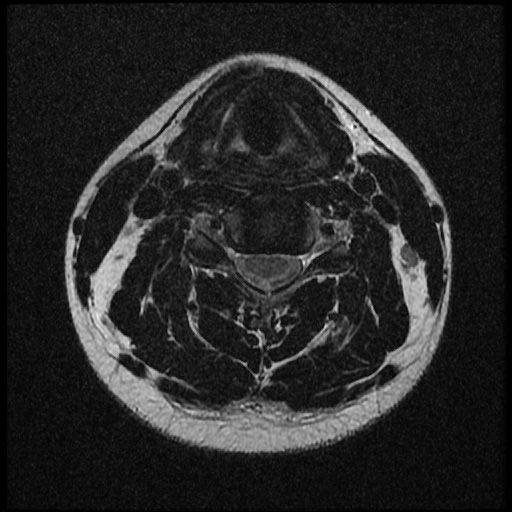

이 MRI 사진은 21년도 사고 당시 찍은 MRI 사진 입니다. 확인 부탁드립니다~

전체 mri를 다 봐여겠지만 보여주신 mri 컷에서는 의미있는 경추 디스크탈출이 보이지 않습니다.